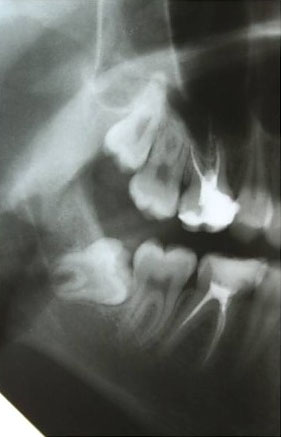

— ортопантомография или, что лучше, конусно-лучевая компьютерная томография. По данным рентгенологического обследования можно определить стадию формирования зуба, направление его движения, отношение к прилежащим структурам, соседним зубам, а также форму и размер образовавшейся под капюшоном полости.

— по данным рентгенодиагностики (КЛКТ или ортопантомограммы) зуб находится в стадии прорезывания (верхушки корней не сформированы), ось прорезывания зуба имеет более-менее правильное направление, его коронковая часть не повреждена кариесом.

— если по данным рентгенологической диагностики причинный зуб имеет сформированную корневую систему, зуб явно уже не прорезывается или, что хуже — упирается коронковой частью в наружную косую линию, соседний зуб или куда-нибудь еще